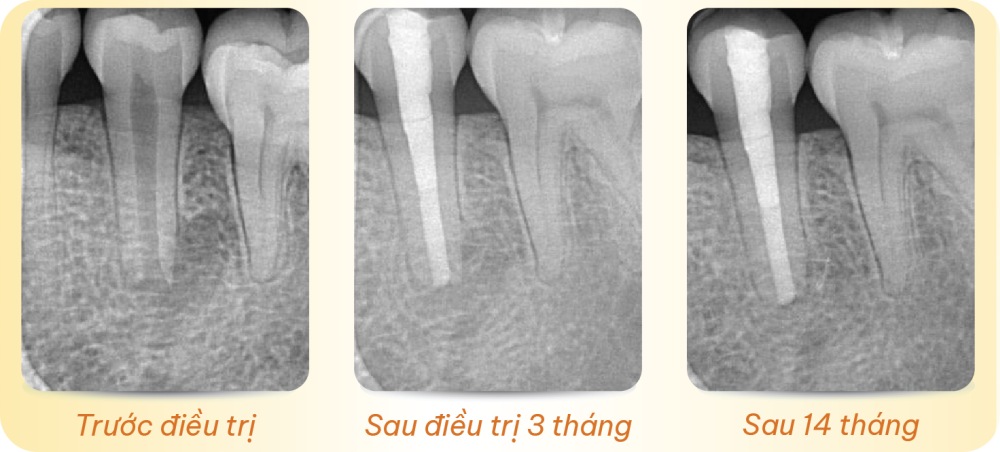

Trước điều trị – Sau điều trị 3 tháng – Sau 14 tháng